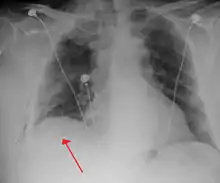

![]() تبين الأشعة السينية للصدر وجود استرواح الصدر على اليمين (يسار الصورة)، حيث تبين أيضًا غياب علامات الرئة لوجود هواء حر داخل الصدر. A large right-sided spontaneous pneumothorax (left in the image). An arrow indicates the edge of the collapsed lung | |

الأشعة السينية على الصدر

عادة ما يكون التصوير الشعاعي العادي للصدر، بإشعاع الأشعة السينية من الخلف (من الخلف للأمام) هو أنسب فحص في البداية. وعادة ما يتم تنفيذ ذلك خلال الشهيق (مع كتم النَفَس). لأن التصوير بالأشعة السينية أثناء الزفير (بعد خروج الهواء) لا يعطي أي معلومات إضافية.[12][13] إذا لم تُظهر الأشعة السينية الساقطة من الخلف للأمام استرواح صدري، ولكن كان هناك شكوك قوية في وجوده، يتم عمل أشعة سينية جانبية ( بإسقاط الأشعة من الجانب)، ولكن هذه ليست الطريقة الروتينية.[13][17] ومن المألوف وجود انحراف المنصف (التركيب بين الرئتين التي يحتوي على القلب، والأوعية الدموية الكبيرة، والممرات الهوائية الكبيرة) بعيدا عن الرئة المتضررة بسبب اختلافات الضغط. لذا فإن هذا الانحراف ليس دليلا على حدوث استرواح الصدر الضاغط، إنما يتحدد أساسا عن طريق مجموعة من الأعراض بالإضافة إلى نقص الأكسجين، والصدمة.[12]

عادة ما يتم إدراج أنابيب الصدر في حالات استرواح الصدر الرضحي. وتزيد الحاجة إلى التنفس الصناعي من خطر استرواح الصدر الضاغط، ويصبح إدخال أنبوب الصدر إلزامي.[12][27] وينبغي تغطية أي جرح مفتوح في الصدر بغطاء محكم، لأنه قد يؤدي إلى استرواح الصدر الضاغط بنسبة كبيرة. يجب استخدام ضمادة تسمى "ختم أشِرمان"، لأنه اتضح أنها أكثر فعالية من الضمادة "ثلاثية الجوانب" المتعارف عليها. وختم أشرمان هو جهاز مصمم خصيصا يلتصق بجدار الصدر، ومن خلال آلية تشبه الصمام، يسمح للهواء بالهروب ولا يسمح له بدخول الصدر.[28]

أنبوب الصدر

يعتبر أنبوب الصدر هو بداية العلاج الأولي لاسترواح الصدر. وعادة ما يتم إدراجه في منطقة تحت الإبطين (الإبط) تسمى "المثلث الآمن"، لتجنب الإضرار بالأعضاء الداخلية. يتم تحديد ذلك المكان بواسطة خط أفقي في مستوى الحلمة، واثنين من عضلات جدار الصدر (العضلة الظهرية العريضة، والعضلة الصدرية الكبيرة)، مع إعطاء مخدر موضعي. ويمكن استخدام نوعين من الأنابيب. في استرواح الصدر التلقائي، يمكن إدخال أنابيب صغيرة (قطرها أصغر من 14ف، 4.7مم) عن طريق تقنية سيلدينجر، ولا تمتلك الأنابيب الأكبر ميزة في هذه الحالة.[13] بينما تستخدم أنابيب أكبر (28ف، 9.3مم) في استرواح الصدر الرضحي.[28]

يجب استخدام أنابيب الصدر في حالات الاسترواح الصدري الأولي التلقائي التي لم تستجب لإبرة الشفط، وفي استرواحات الصدر كبيرة الحجم (> 50٪)، وفي حالات استرواح الصدر الضاغط. وتكون متصلة بنظام صمام أحادي الاتجاه يسمح للهواء بالخروج من الصدر، ولا يسمح له بإعادة الدخول. وقد تتضمن هذه الطريقة زجاجة ماء تعمل كمصيدة للمياه، أو كصمام هيمليتش. وهي لا ترتبط عادة بدائرة ضغط سلبي، لأن ذلك سيؤدي إلى إعادة توسع سريعة في الرئة مما يعرضها لخطر الوذمة الرئوية ("الوذمة الرئوية التوسعية"). ويبقى الأنبوب في مكانه حتى يتوقف خروج الهواء منه لفترة من الزمن، ويتم تأكيد إعادة توسع الرئة بالأشعة السينية.[13][17][23]